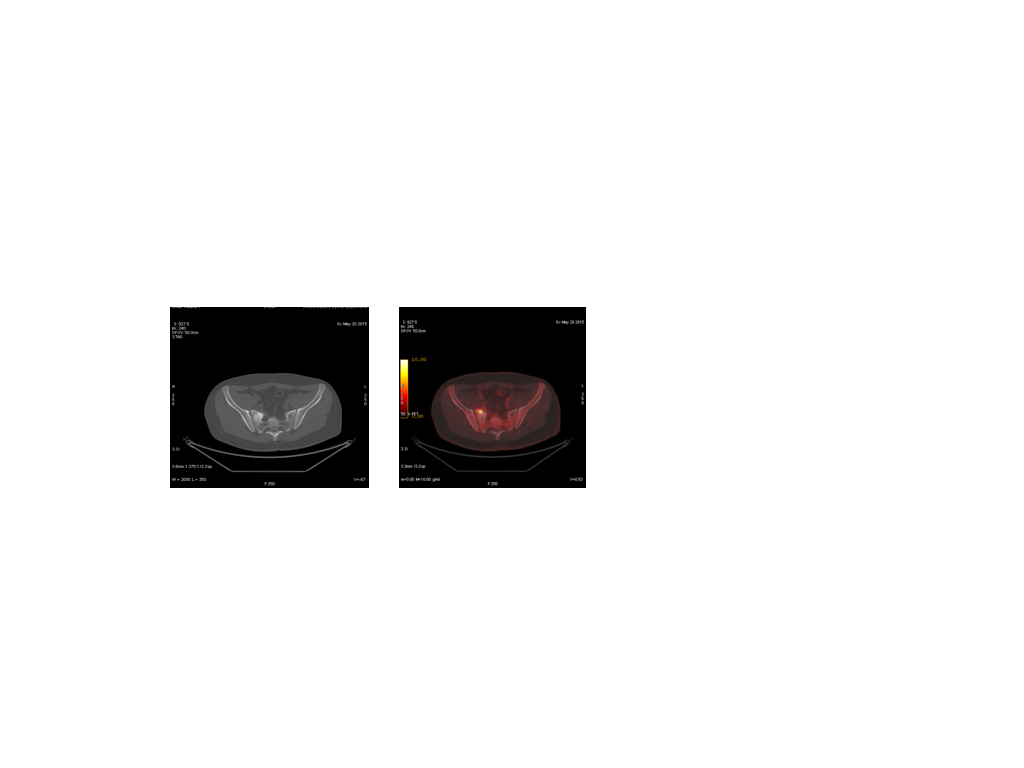

- Pet TC Scan

- Epígrafe de figura 7